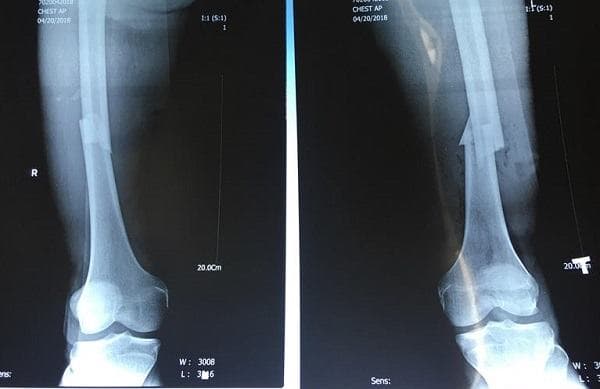

Với trường hợp xương chày gãy hở hoặc tổn thương nghiêm trọng, người bệnh không thể áp dụng phương pháp điều trị nội khoa thì cần phải phẫu thuật cố định xương gãy. Bác sĩ sẽ sử dụng ốc vít, thanh hoặc tấm, nẹp kim loại để cố định xương cẳng chân với nhau.